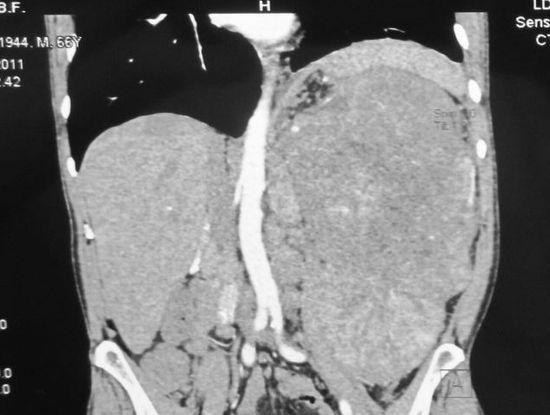

Опухоль левой почки

Опухоль левой почки, выпячивающая переднюю брюшную стенку

Опухоль левой почки, прорастающая брыжейку толстой кишки